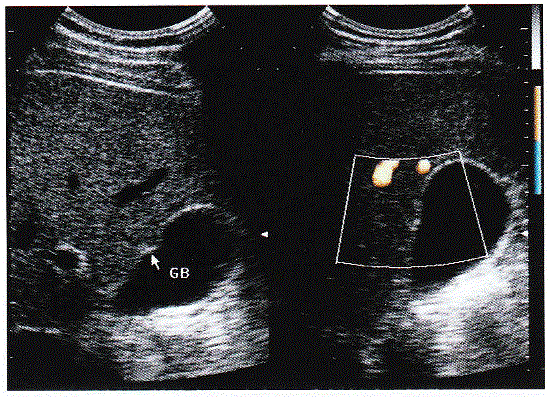

问题 临床资料:女,50岁,常规体检。 超声综合描述:肝右叶胆囊前壁外可见0.8cm×0.6cm稍低回声区,边界清晰,胆囊前壁受其推挤向内凹陷,CDFI:其内未见明显血流信号。见下列彩图。 超声提示:

选项 A.肝腺瘤 B.脂肪肝脂肪分布不均 C.肝硬化增生结节 D.肝结节病

答案 A